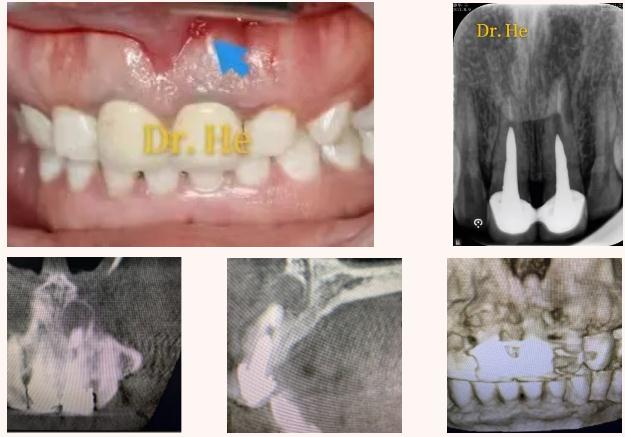

王女士3年前曾因牙痛在外院进行上前牙常规根管治疗,后采取桩核冠修复。近1年来,王女士左上前牙牙龈反复起脓包,经久不愈。辗转多家医院,有的建议取桩核冠进行根管再治疗,有的建议拔除进行种植。为寻求最佳的治疗方法,王女士到我院(包头医学院口腔医院)牙体牙髓科就诊。

牙体牙髓科贺娜医生接诊了王女士,经过详细的问诊和口腔检查后,为患者拍摄了上前牙的根尖片和上颌CBCT。分析病情后制定了治疗方案——显微根尖手术。

患者术后三个月来复查,瘘管闭合,根尖病变范围明显缩小。